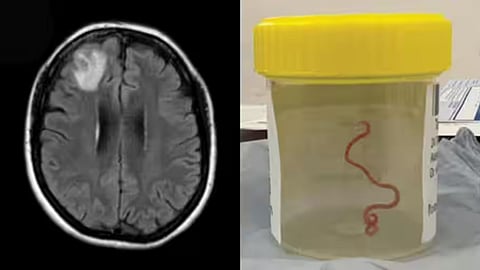

ऑस्ट्रेलियाची राजधानी कॅनबेरा येथे एक विलक्षण घटना उघडकीस आल्याने, वैद्यकीय क्षेत्र हादरले आहे. एका न्यूरोसर्जनने रुग्णाच्या मेंदूमधून 8 सेमी-लांब जिवंत जंत (Parasitic Roundworm), काढला.

कॅनबेरा हॉस्पिटलमधील न्यूरोसर्जन डॉ. हरी प्रिया बंदीचा यांनी न्यू साउथ वेल्समधील 64 वर्षीय महिलेवर ही शस्त्रक्रिया केली.

या महिलेला सुरुवातीला ओटीपोटात दुखणे, जुलाब आणि ताप यासारखे त्रास सुरू झाले. स्थानिक रुग्णालयात उपचार सुरू असलेल्या या रुग्णाला होणारा त्रास वाढला. त्यामुळे तिला अखेरीस कॅनबेरा रुग्णालयात उपचारासाठी नेले, जिथे तिच्या मेंदूच्या एमआरआय स्कॅननंतर, मेंदूची शस्त्रक्रिया करण्याची आवश्यक्ता जाणवली.

महिलेची शस्त्रक्रिया सुरू असताना न्यूरोसर्जन डॉ. हरी प्रिया बंदीचा यांना मेंदूमध्ये एक वळवळणार जिवंत जंत सापडला.

सर्जिकल पथकाला 3 इंच लांबीचा, चमकदार लाल, राउंडवर्म सापडला ज्याला शास्त्रज्ञ ओफिडास्कॅरिस रॉबर्टसी असे म्हणतात.

या महिलेच्या मेंदूत अशा प्रकारचा जंत सापडल्याने वैद्यकीय क्षेत्रात खळबळ उडाली आहे. कारण हा जंत सामान्यतः सापांमध्ये आढळतो.

राउंडवर्मचा हा विशिष्ट प्रकार कार्पेट पायथन्समध्ये आढळतो, जो कंस्ट्रक्टरची एक मोठी प्रजाती आहे. ते ऑस्ट्रेलिया, इंडोनेशिया आणि पापुआ न्यू गिनीमध्ये आढळतात.